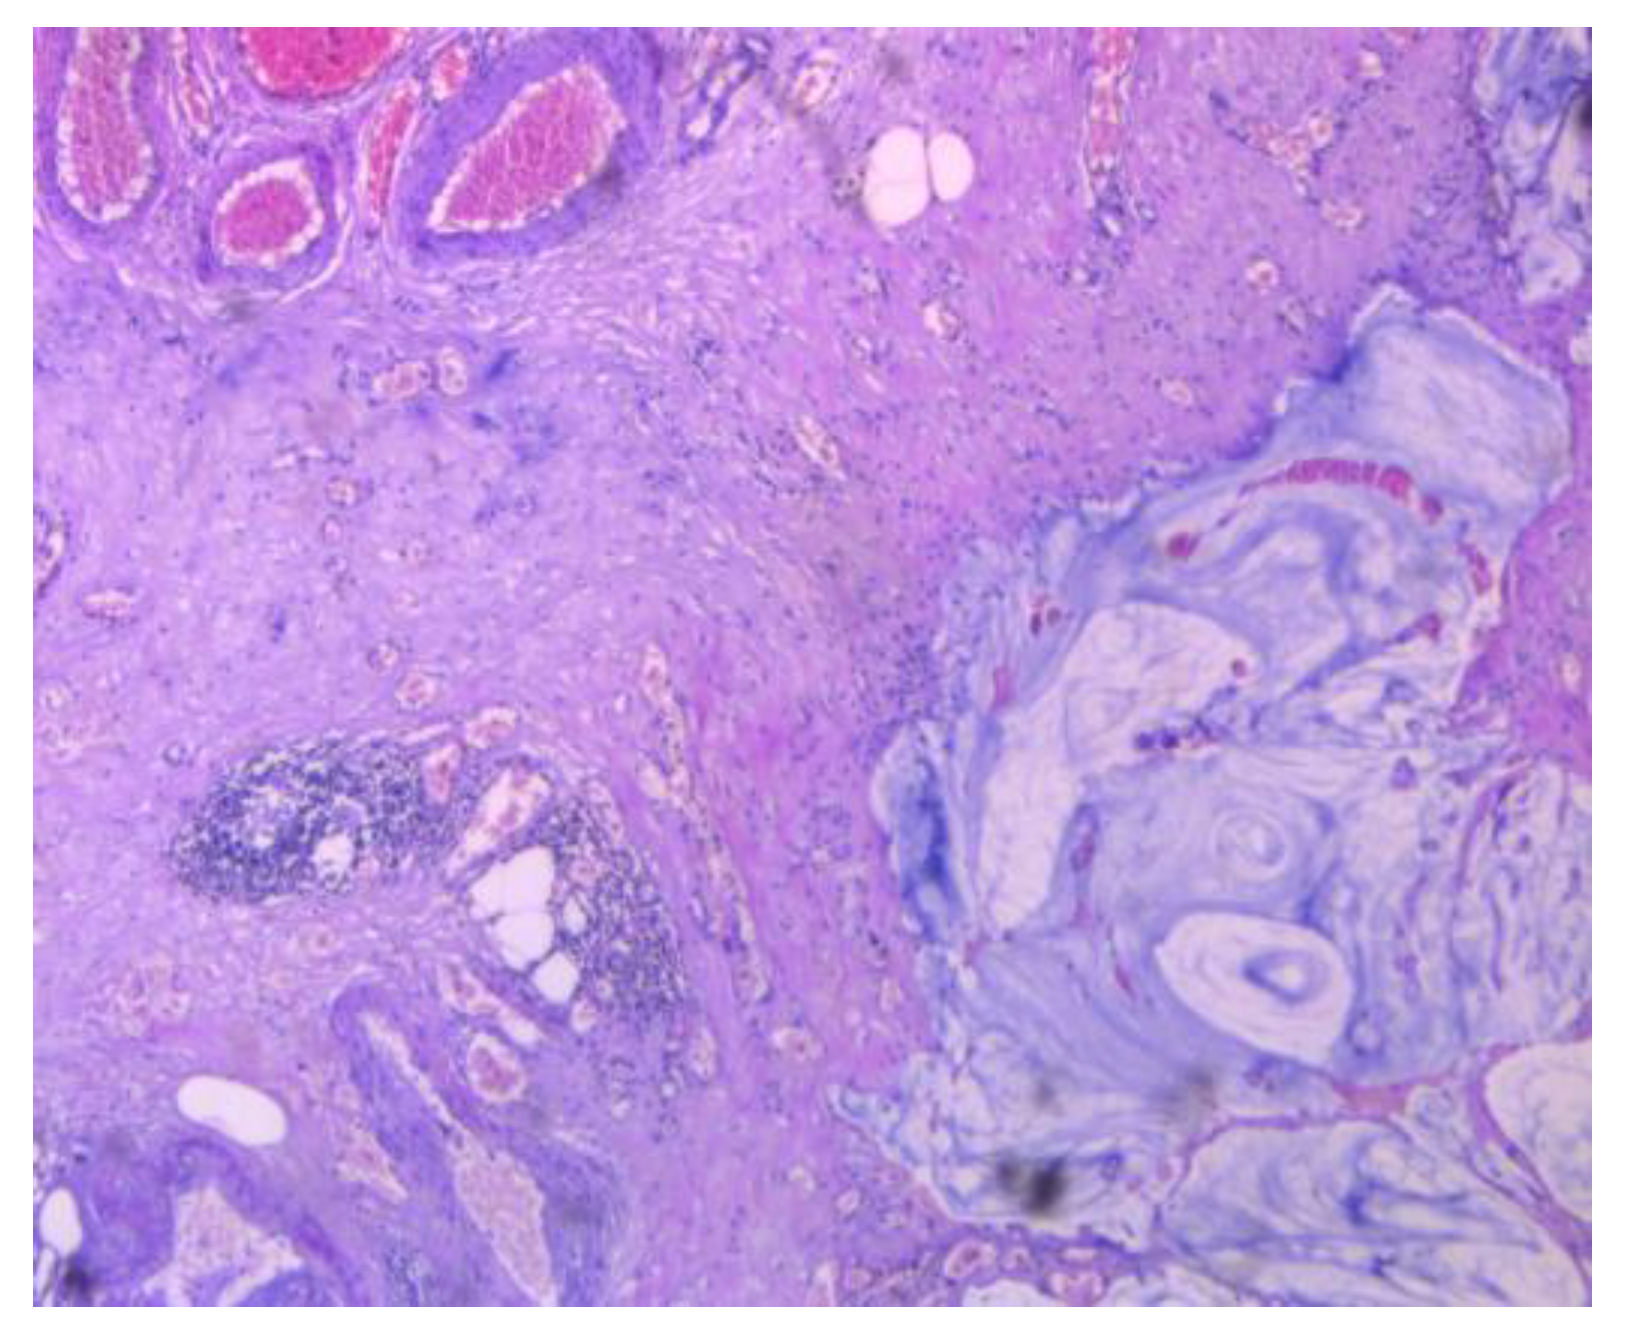

3.1.4. Malignant Transformation of an Ovarian Primary Mature Cystic Teratoma (MCT)

3.1.5. Appendiceal Mucocele with Peritoneal Dissemination Mimicking an Ovarian Tumor with Peritoneal Carcinomatosis

3.2.2. Clinical and Pathology Findings